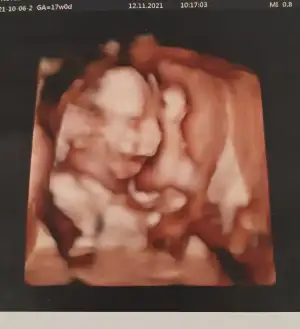

Anaaam eli uzunde ovusturuyir sanki uyanamamis beyfendi 😇👼

Birde baya cabuk buyuyolar ki baksana ilk fotograf 15+3, ikincisi 17haftalikken. Yani dusunuyorum 3 aralikta tam 20 hafta olacak, ne kadar buyumustur Allah bilir 😍 17 haftalikkrn bildigin bal yanak 😋

Allahım küçücük bir canlının kolu bacağı kulağı falan var nasıl bi mucize taşıyoruz içimizde 🧿🧿🧿🧿🧿 kocaman olmuştur artık annesi güzel güzel pozlar verir insallah detaylı ultrasonda 😍